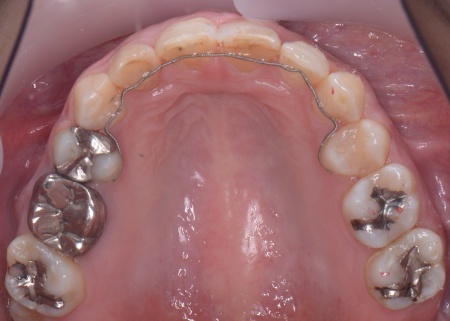

30代女性 出っ歯と開咬に対しアンカースクリューを用いたワイヤー矯正で治療した症例

拝見したところ、上前歯が大きく前に出ている上顎前突であり、上下の前歯が噛み合わずに口を閉じても前歯同士が接触しない「開咬(かいこう)」の状態でした。

矯正治療終了後は、歯が元の場所に戻らないよう上下前歯に保定装置(リテーナー)を装着し、治療を終了しています。